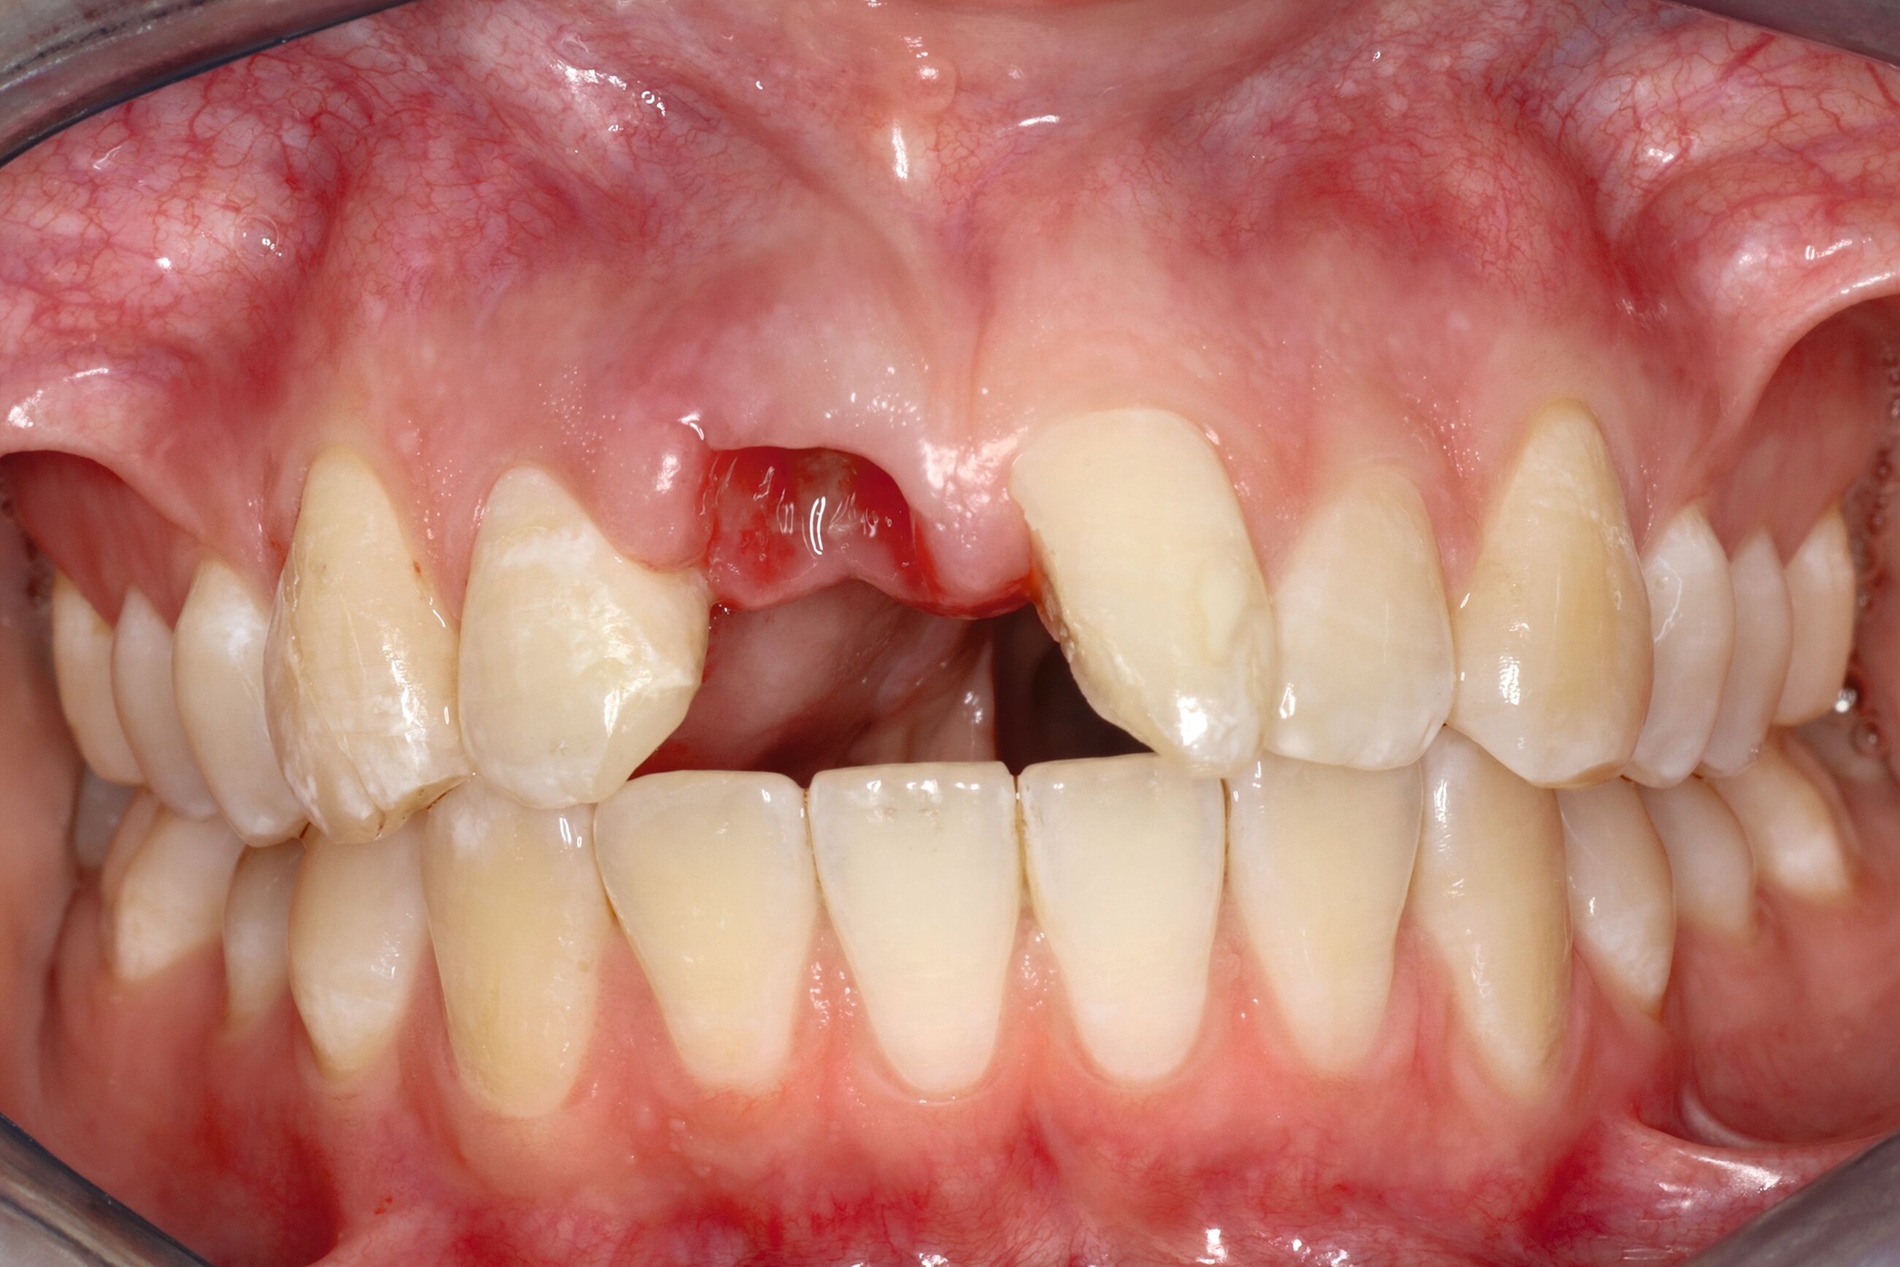

Nach einem vollständigen Zahnverlust oder auch nach einer erfolgten Dekoronation ankylosierter Zähne bietet sich insbesondere bei jungen Patienten die Versorgung mit einer Adhäsivbrücke an. Die einflügelige Adhäsivbrücke stellt eine minimalinvasive Möglichkeit zur Versorgung der Lücke bei Schneidezähnen dar (Abbildung 3). Für diese Versorgungsform liegen sehr gute Langzeitüberlebensraten von über 98 Prozent vor [Kern et al., 2017]. Einflügelige Adhäsivbrücken haben im Vergleich zu zweiflügeligen Adhäsivbrücken eine signifikant höhere Überlebensrate [Thoma et al., 2017].